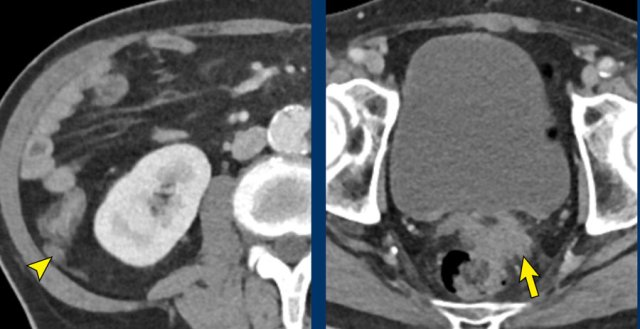

CT is not sensitive for the detection of small peritoneal lesions, but larger lesions may be noted.

Images

Peritoneal

metastases in the right paracolic gutter (arrowhead) and in the rectovesical

space (arrow) in a patient with locally advanced pancreatic cancer (not shown).

In the presence of distant metastases curative intended treatment of LAPC (systemic

therapy with possible subsequent resection) is no longer an option.